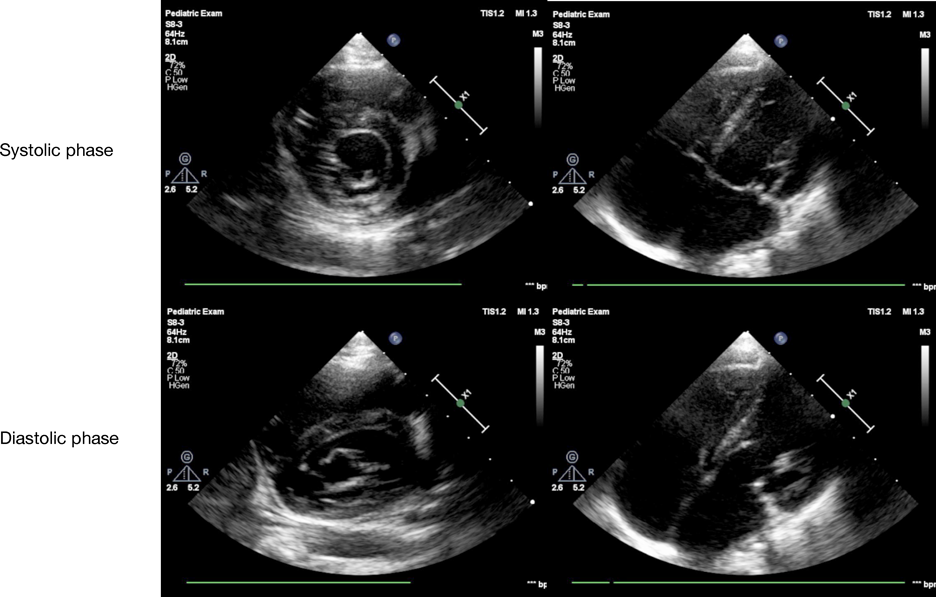

心臓超音波検査(Fig. 1)

Pediatric Cardiology and Cardiac Surgery 35(1): 52-58 (2019)

Fig. 1 Preoperative echocardiogram of case 1

Moderate mitral valve regurgitation is shown. Posterior mitral leaflet, especially middle part (P2), is hypoplastic.

後尖,特にP2を中心とした低形成によるmoderate MRを認めた.僧帽弁輪径は20.0 mm(114% of normal)であった.